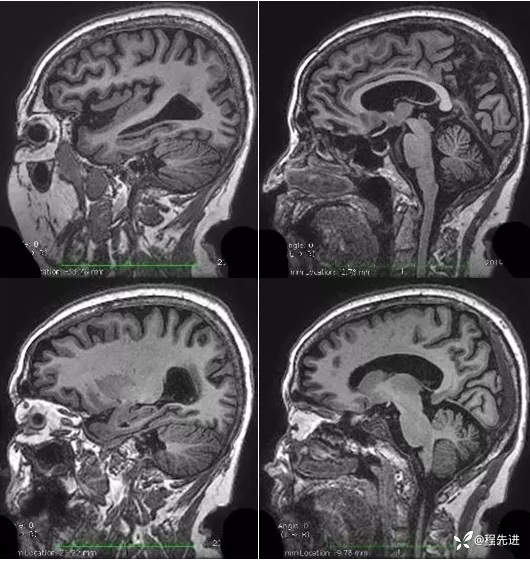

T1 FSPGR: